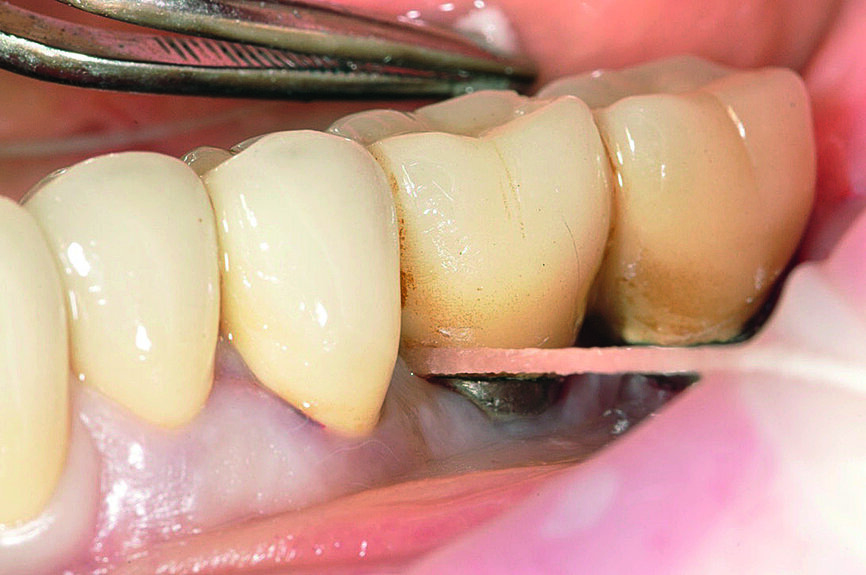

Fig. 3 : Excès de ciment autour de l‘implant

Fabrication et assemblage de la prothèse

Le prothésiste dentaire doit travailler en contact direct avec le chirurgien-dentiste afin de créer des espaces permettant un nettoyage confortable et esthétiquement plaisants, adaptés au patient. Après avoir reçu les instructions et les informations de l’hygiéniste bucco-dentaire, les patients doivent être en mesure de nettoyer leurs prothèses quotidiennement et presque sans effort afin de maintenir leur santé orale.13 Un autre facteur important associé aux signes cliniques de péri-implantite est l’excès de ciment.14–17 Pour éviter cet excès, les limites marginales de la restauration doivent être situées au niveau ou au-dessus du bord péri-implantaire de la muqueuse ; sinon l’excès de ciment doit être éliminé.18 En dépit de la littérature internationale démontrant l’intérêt accru que suscite l’excès de ciment considéré comme l’un des facteurs clés dans l’étiopathogénie de la péri-implantite, un protocole standard guidant le clinicien dans cette délicate procédure d’élimination doit encore être mis en place. Selon l’auteur, la technique de scellement demande du temps, de l’attention, le port de loupes binoculaires et de la minutie. C’est pourquoi un protocole précis, dépendant de la composition du ciment, doit être publié (Figs. 7 et 8).